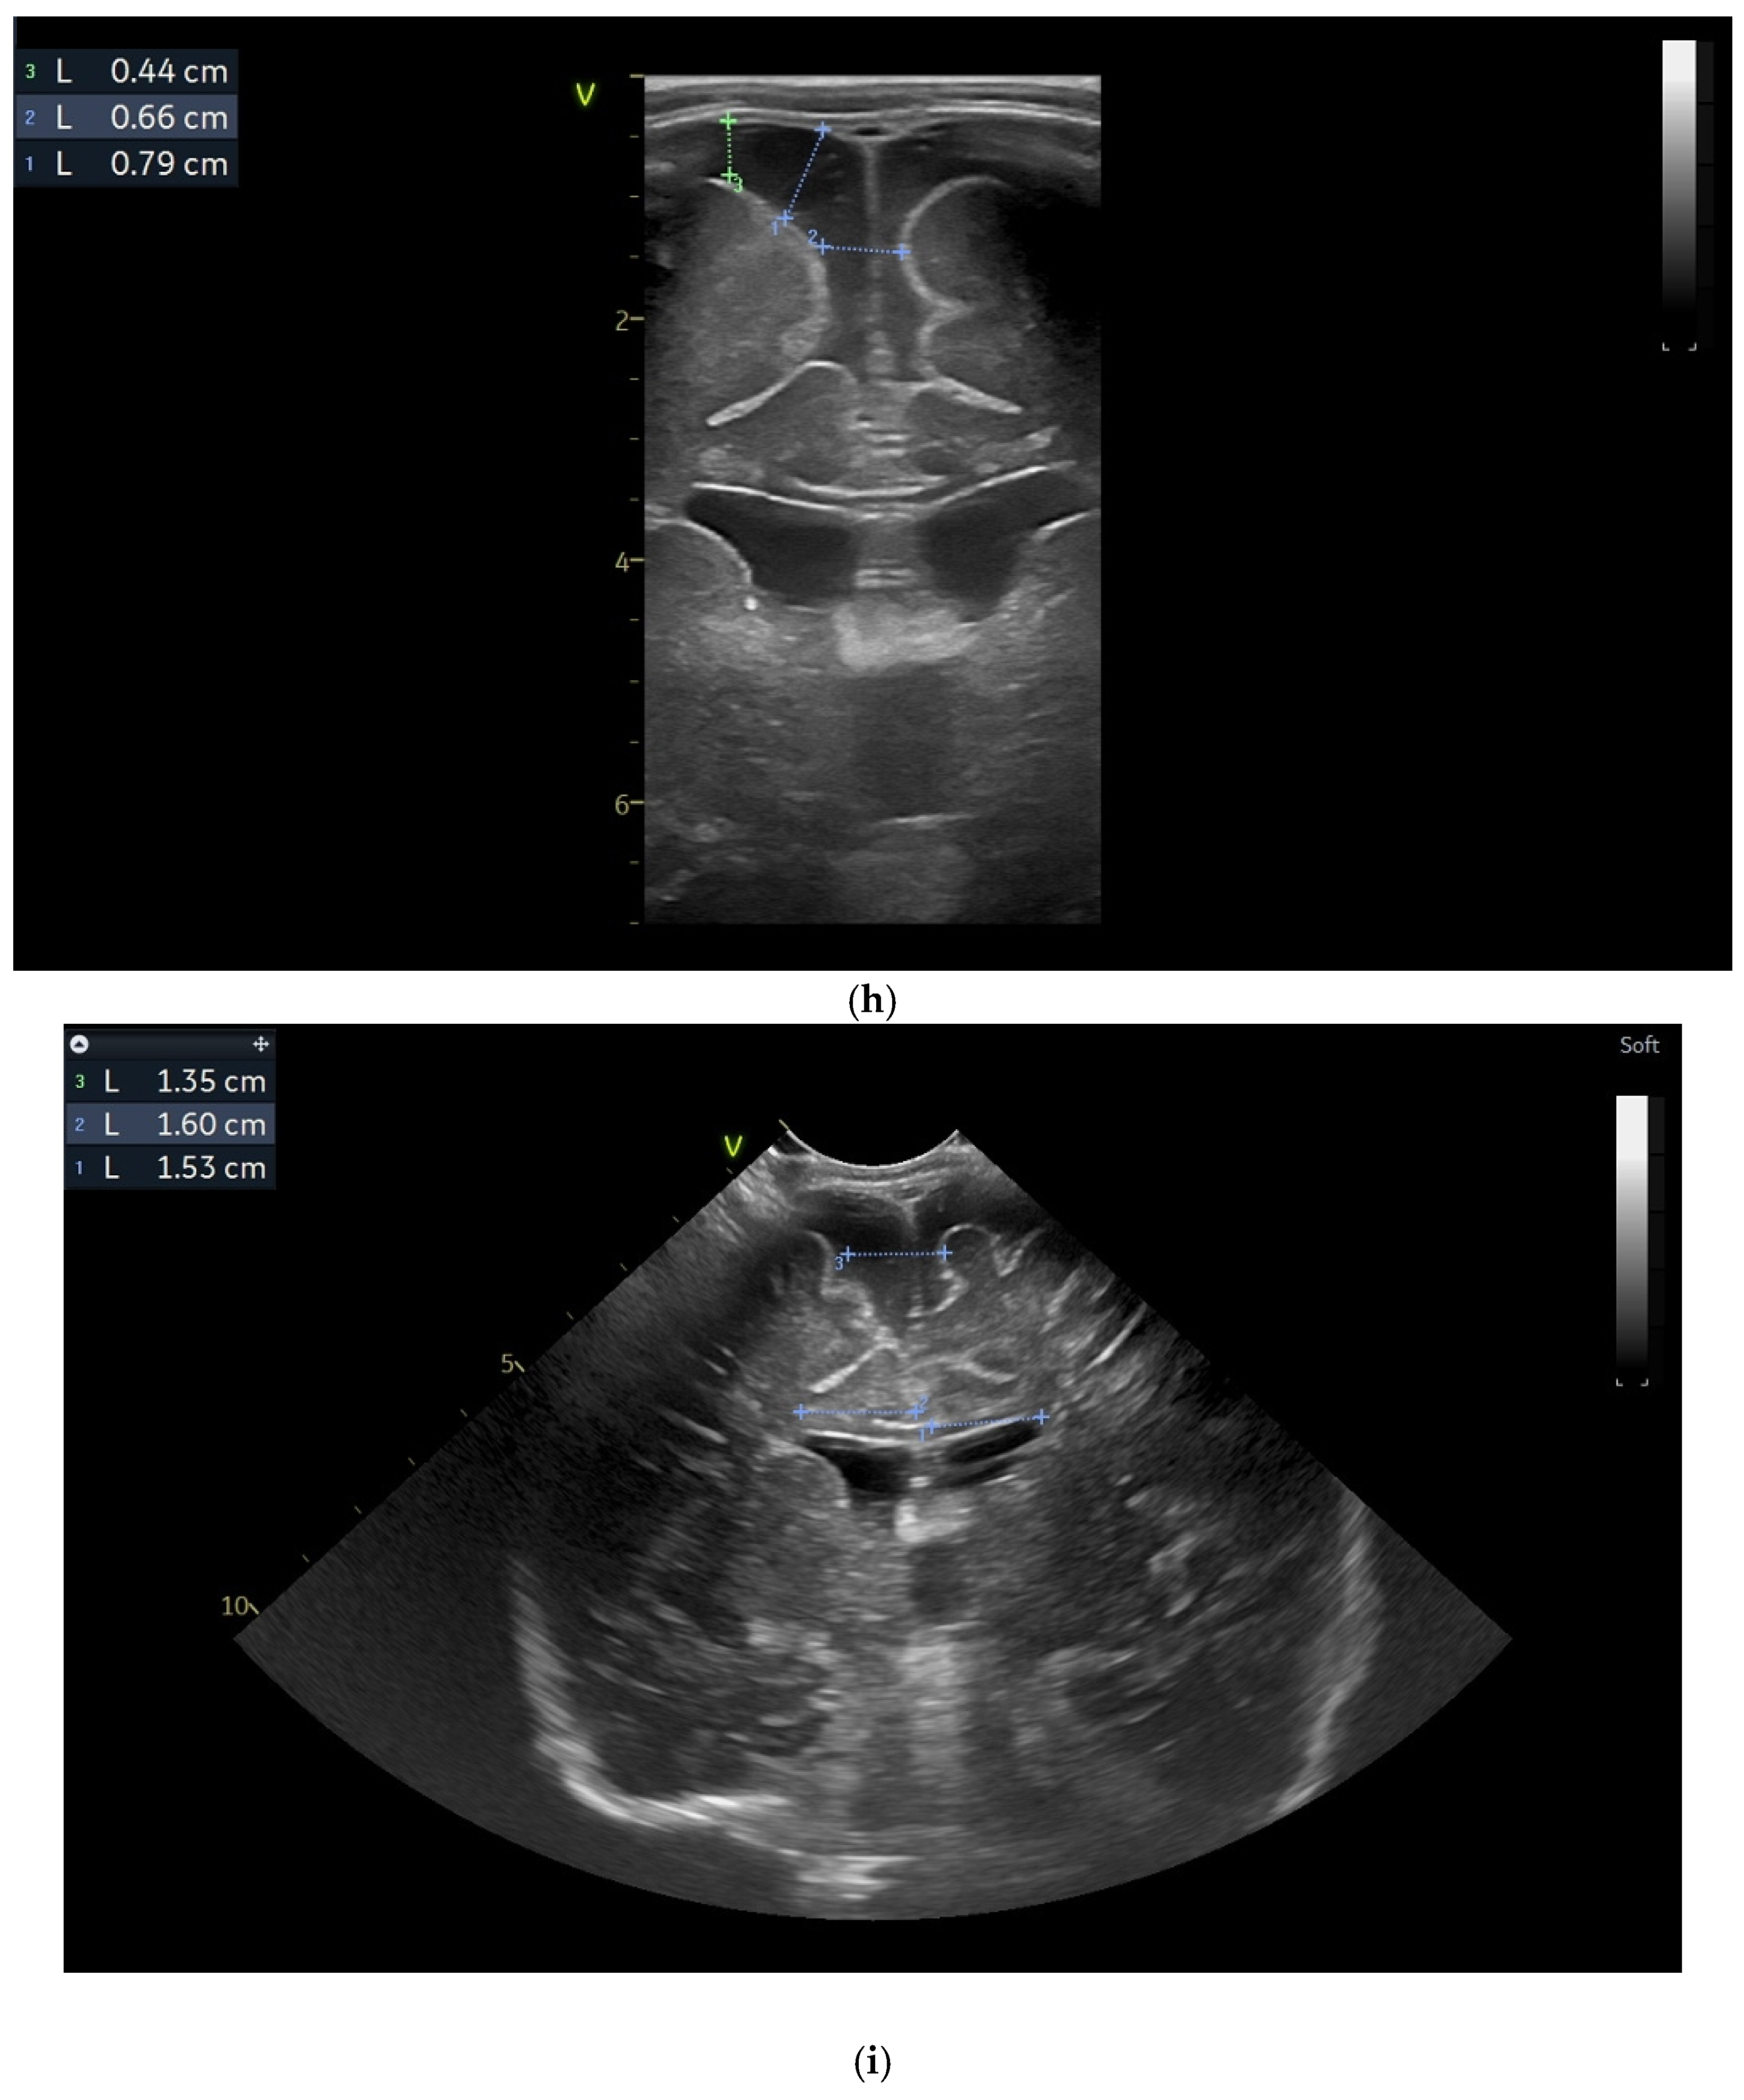

(a) Day one. Cranial ultrasound. Sagittal view. A left frontal conatal cyst can be observed. IHF—interhemispheric fissure. CG—cingulate gyrus. CC—corpus callosum. CSP—cavum septum pellucidum. TCG—thalamic-caudate groove. MF—Monroe foramina. SF—Sylvian fissure. Yellow arrow—conatal cyst (personal image collection). (b) Day three. Cranial ultrasound. Coronal view. Bilateral ventricular dilatation. Yellow arrows—hyperechoic images can be seen at the level of the thalamic-caudate groove and within the ventricles (personal image collection). (c) Day three. Cranial ultrasound. Coronal view. Orange arrows—bilateral periventricular hyperechoic images (personal image collection). (d) Day three. Cranial ultrasound—Doppler examination. Sagittal view. CC—corpus callosum. FL—frontal lobe. LV AH—lateral ventricle anterior horn. V 3—third ventricle. V 4—fourth ventricle. OL—occipital Lobe. Yellow arrow—presence of color Doppler signal within the Sylvian aqueduct (personal image collection). (e) Day 19. Cranial ultrasound. Sagittal view (left). Yellow arrows—conatal cysts. Pink arrows—PVL lesions (personal image collection). (f) Day 19. Cranial ultrasound. Sagittal view (left). Yellow arrows—conatal cysts. Pink arrows—PVL lesions (personal image collection). (g) Follow-up examination at term corrected age. Cranial ultrasound. Coronal view. Slight dilation of the lateral ventricles. IHF—interhemispheric fissure. CG—cingulate gyrus. CC—corpus callosum. CSP—cavum septum pellucidum. LV—lateral ventricle. MF—Monroe foramina (personal image collection). (h) Second follow-up examination. Cranial ultrasound. Coronal view. Dilation of interhemispheric fissure and subarachnoid space. D1—sinus–cortical width measurement. D2—interhemispheric width measurement. D3—cranio-cortical width measurement (personal image collection). (i) Third follow-up examination. Cranial ultrasound. Coronal view (left). D1—dilation of interhemispheric fissure. D2, D3—Levine index measurement (personal image collection). (j) Cranial ultrasound. Sagittal view (right). Normal brain structures (personal image collection). (k) Head circumference-for-age. “X” symbols represent the measurements performed from birth and follow-up examinations (personal image collection) [28].

On day three of life, the CUS displayed a bilateral germinal matrix hemorrhage with more than 50% of the ventricular volume being occupied by blood. Periventricular hyperechoic images could be observed as well (Figure 2b,c).

On the fourth day of life, a Doppler examination showed the presence of a signal within the third ventricle (Figure 2d).

A series of four lumbar punctures were performed during the patient’s in-stay to relieve the intracranial pressure—expressed as a bulging fontanelle. The first three lumbar punctures presented hemorrhagic CSF, while the last lumbar puncture showed sero-citrine CSF. Afterwards, the ventricular dimensions stabilized; however, small visible PVL lesions were visible on the CUS examination, in addition to the two conatal cysts that were observed (Figure 2e,f).

The first follow-up CUS examination was performed at the term-equivalent age (corrected gestational age) and revealed a slight dilation of the lateral ventricles (Figure 2g). The neurologic examination showed normal development for the corrected gestational age and mild plagiocephaly.

The next follow-up examination was performed two months from birth at the term-equivalent age and the CUS examination showed dilation of the interhemispheric fissure and the subarachnoid space (Figure 2h). Plagiocephaly, torticollis, mild motor development delay, and hypertonia in the lower limbs were observed.

Four months after the first follow-up examination, the CUS revealed normal brain structures. The general movement examination showed absent fidgety movements, while the neurological examination showed a global developmental delay with hypertonia of the limbs predominantly at the level of the left side of the body (Figure 2i,j).

On the fourth follow-up examination, the dilations were still visible. The neurological examination revealed mild trapezius muscle retraction and mild hypertonia at the level of the inferior limbs. The fifth follow-up examination—performed at one year after birth—revealed mild motor developmental delay.